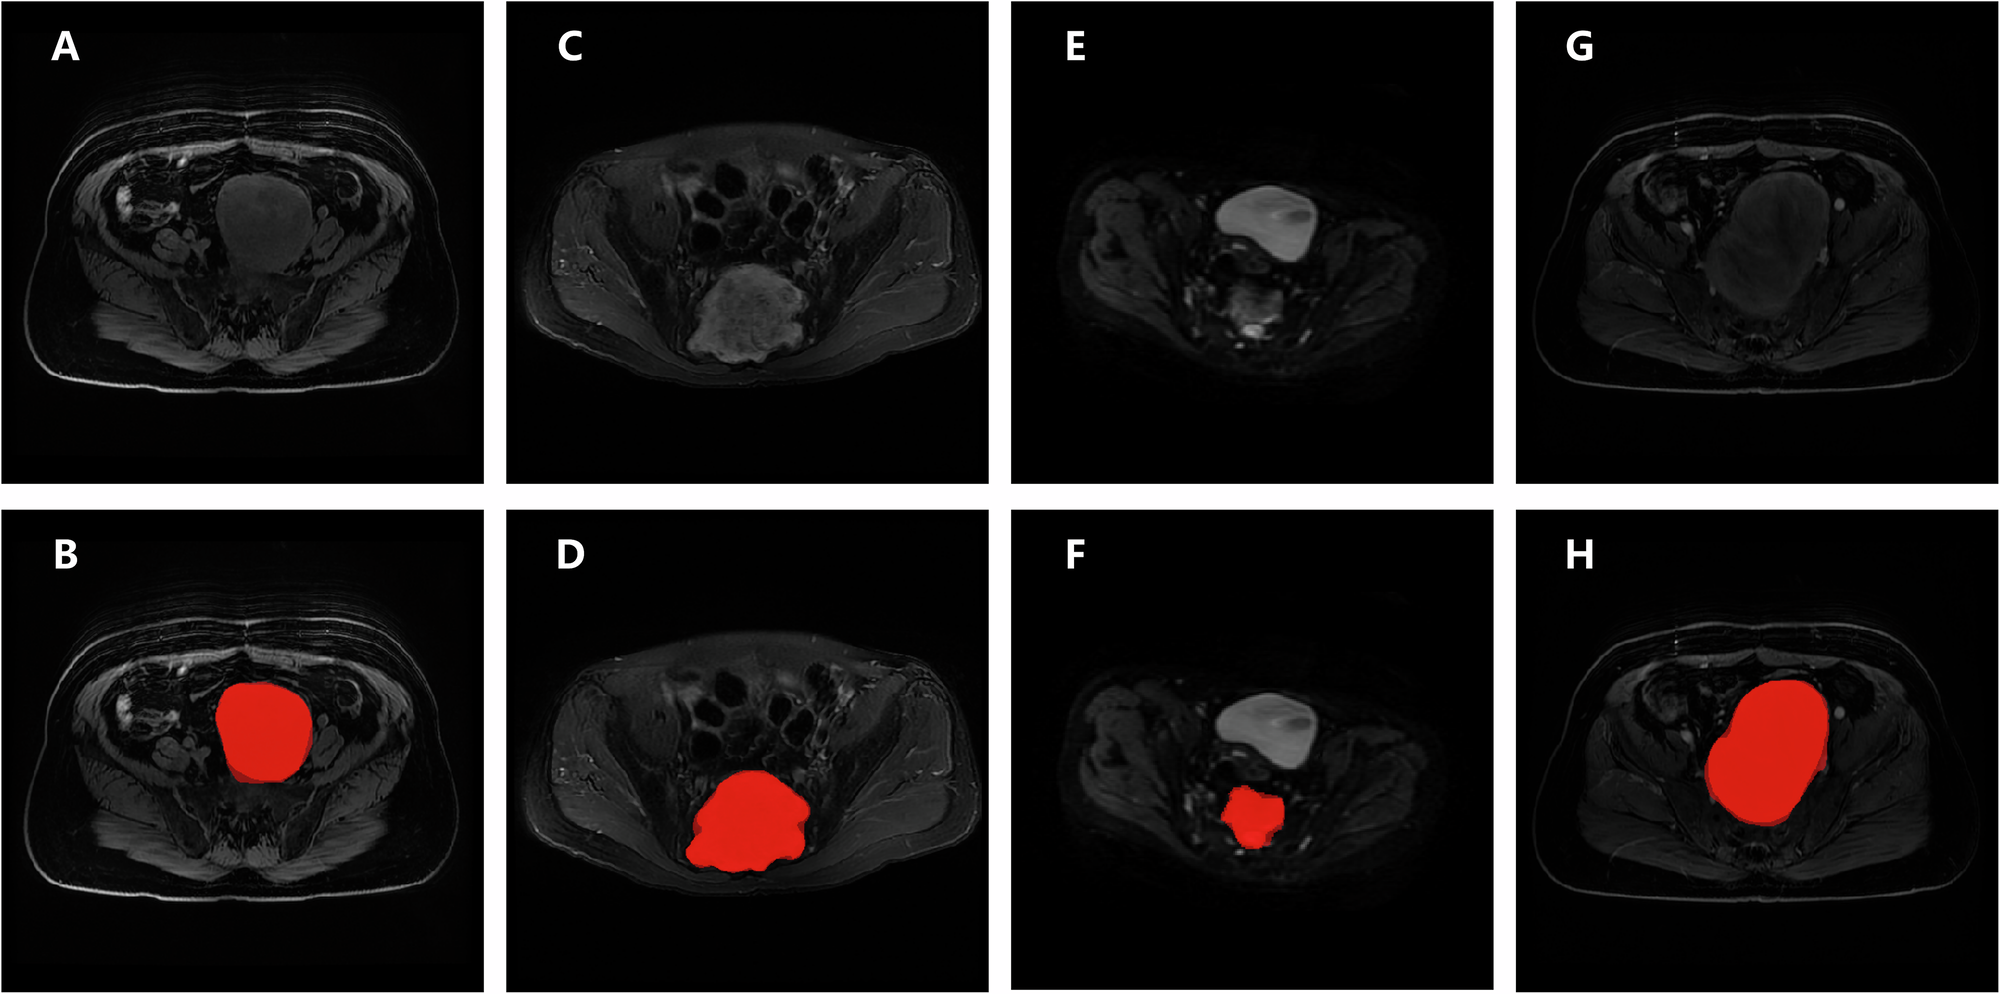

Fig. 1: Demonstration of the segmentation model’s predictions.

A, B T1-w images of a 62-year-old female patient with neurofibroma; C, D T2-w images of a 44-year-old male patient with mucinous papillary ependymoma; E, F DWI images of a 45-year-old female patient with schwannoma; G, H CET1-w images of the same patient as (A) and (B). The second line shows T1-w, T2-w, DWI and CET1-w images (from left to right) with model’s segmentation and radiologist’s segmentation, darker color represents radiologist’s segmentation.